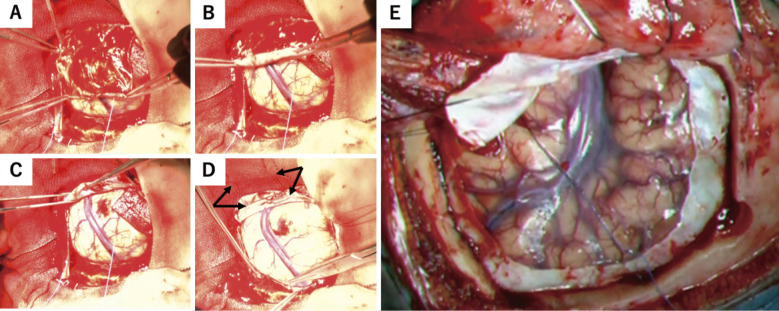

Dural dryness makes suturing difficult during dural closure after craniotomy. In this case, dural plasty is often performed using a membrane taken from the surrounding tissue (e.g., fascia or periosteum) or an artificial replacement membrane. Herein, we introduce our novel "roll-up technique" to reduce the utilization of substitute membranes and explore its effectiveness in dural closure. We retrospectively examined the medical records of 50 patients who underwent craniotomy for the first time for supratentorial intracranial lesions between 2015 and 2022. Furthermore, we divided them into two groups: (1) the conventional technique group, which consisted of patients in whom the dura mater was flipped after incision and protected with a moistened gauze (n = 23), and (2) the roll-up technique group, which consisted of patients in whom the dura mater was incised in a U shape, rolled up, and protected with a moist gauze (n = 27). After surgery, we compared the success rates of primary closure, operating time, craniotomy area, and percentage of complications (e.g., cerebrospinal fluid [CSF] leakage or infection) between the groups. Dural closure without dural substitutes using the roll-up technique had a higher success rate than that using the conventional technique (26/27 [96.3%] cases vs. 14/23 [60.9%] cases; P = 0.003). Postoperative CSF leakage or infection did not occur, and no statistically significant difference was observed in the operating time between the groups (P = 0.247). The roll-up technique for dural closure may effectively prevent post-incisional dural shrink after craniotomy.